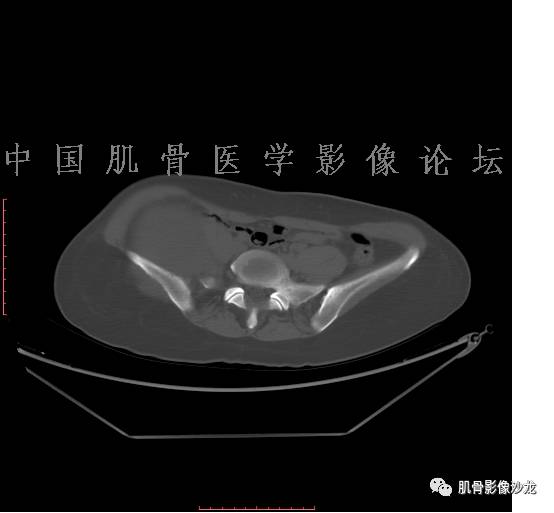

患者2月前无明显诱因下感右腿疼痛、麻木,疼痛呈持续性,发作时无法行走,休息后可缓解。当时无明显肿块,患者遂至当地医院就诊,查X片见右髂骨骨质破坏。6周前患者自觉右髋部渐大肿块,初肿块较小,后肿块逐渐增大,现肿块约12*10cm大小,有压痛。患者遂至我院就诊,查MRI:右髂骨异常信号,伴软组织肿块。ECT、肺CT未见转移。现患者为求进一步治疗,门诊拟“右髂骨肿块 ”收治入院。 患者发病来,神清,精神可,胃纳夜眠可,二便无殊,体重无明显变化。

1、软骨肉瘤可以有膨胀性骨质破坏(病例3,4),可以有溶骨性骨质破坏(病例2),局部皮质因为破坏变薄,中断 ;

2、软骨基质T2WI高信号,软骨小叶分叶状,也就会出现高老师提到的骨内膜扇贝形压迹。一般认为骨内膜扇贝形压迹超过骨皮质厚度的2/3是软骨肉瘤在长管状骨的特征性表现。如上图。3、软组织肿块或肿胀;

4、 钙化,环形,弓形,边缘模糊 ;

5、增强后进行性延迟,不均匀分割状强化, 会强化的纤维间隔,软骨小叶不会强化,关于老师们说到的钙化,软骨肉瘤不一定会有钙化 。